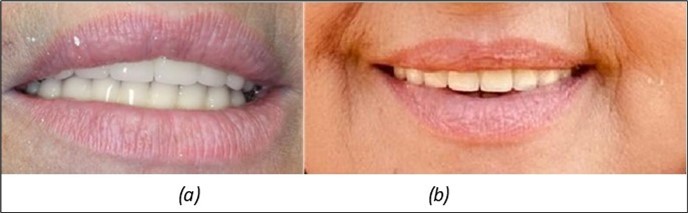

Figure 7.(a) The aesthetic appearance of the patient from the front 4 days. b) 3 years after

The results of rehabilitation treatment with corticobasal and compressive implants with a polished surface after the failure of two stage implants were highlighted over a period of 3 years and 3 months as being very good (Figure 14, Figure 15), with the patient completing a satisfaction survey in this regard. Certainly, it is necessary to continuemonitoring these results in the long term.